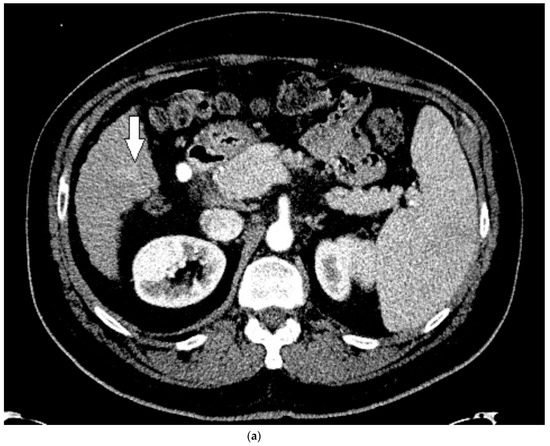

His liver function continued to decline during his stay, and within two weeks he received a deceased donor liver transplantation. HCC within the explanted liver was confirmed by histopathological examination, corresponding to the findings on CEUS. Upon review of the prior CT, for which a reduced contrast bolus (75 mL Omnipaque™ 350) was given due to his chronic renal disease, the tumor was subtle but faintly visible with the knowledge of its location based on the findings on CEUS (Figure 6).

Figure 6.

Patient 3 CT images using liver windows to highlight the subtle enhancement and washout of the lesion seen on CEUS (white arrow): (a) late arterial phase axial contrast-enhanced CT; (b) 3 min delayed phase.